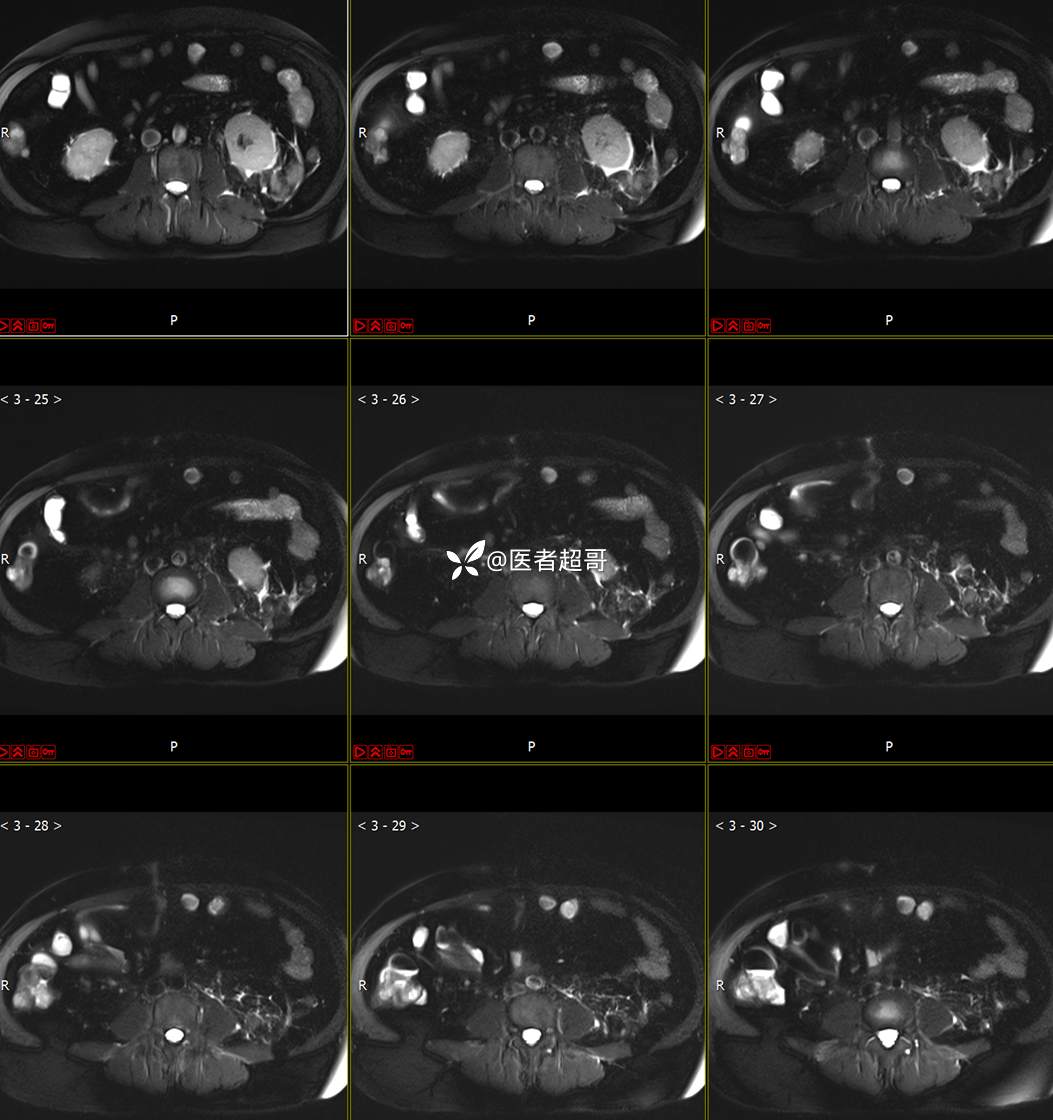

主 诉:查体发现左肾肿物9天。

现病史:患者9天前于附属医院行常规腹部CT检查时,发现左肾占位性病变并肾周脂间隙软组织增多,自述无明显腰腹部不适,无尿频、尿急、尿痛及肉眼血尿,未予特殊治疗,患者近期无头晕头迷,胸闷气急,腹胀腹泻及其他部位明显不适,遂至我院就诊,门诊以“肾肿物”收入院,患者自发病以来,精神可,睡眠饮食可,大便正常,体重无明显减轻。